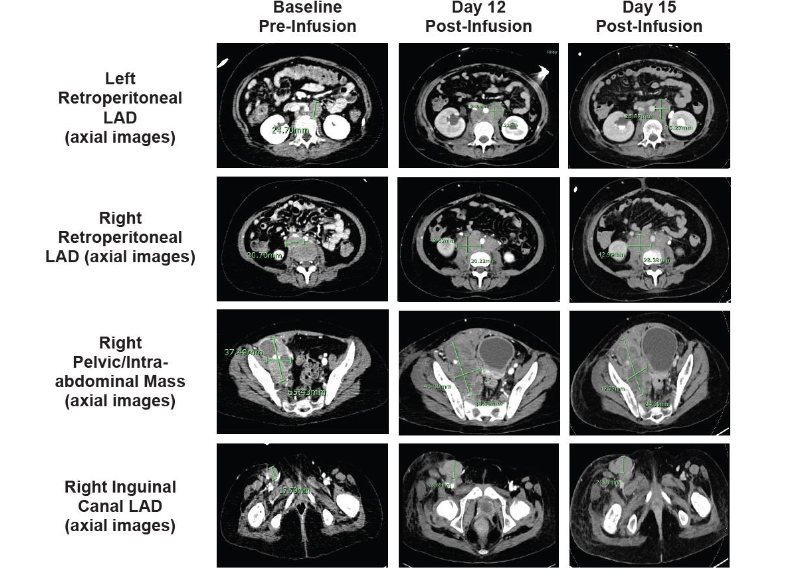

On day 8, the patient experienced progressive swelling of the mouth and gums with gingival bleeding, oral airway obstruction, transient difficulty breathing, recurrent swelling of scalp lesions, and profound nausea/vomiting. The patient simultaneously developed lower right extremity swelling and was found to have a superficial saphenous vein thrombus on ultrasound. Cranial CT (Figure 3) showed progression of existing intracranial extramedullary sites. A marked increase in known retroperitoneal disease was also observed (not shown). Given the prior reduction in extramedullary chloromas, the patient received a third tocilizumab dose (8 mg/kg) in addition to dexamethasone (10 mg IV every 6 hours). The patient’s scalp lesions decreased in size. Lower right extremity swelling and nausea/vomiting resolved completely over 36 hours.On day 12, the patient again had lower right extremity swelling. Repeat abdominal CT (Figure 4) showed a mild increase in adenopathy, with complete inferior vena cava and right external iliac vein occlusion. The patient received siltuximab (400 mg IV every 72 h) given the substantially longer half-life than tocilizumab. Unfortunately, the patient experienced no notable response and underwent emergency radiation therapy (2 Gy over 2 consecutive days). No substantial improvement in lower right extremity swelling or size of retroperitoneal adenopathy was observed at day 15 (Figure 4).

Figure 4. A. Baseline and post-infusion CT scans show marked progression of known retroperitoneal disease. Baseline pre-infusion (CT) and post-infusion (CT) scans are shown. Arrows indicate areas of known retroperitoneal disease; CT, computed tomography.